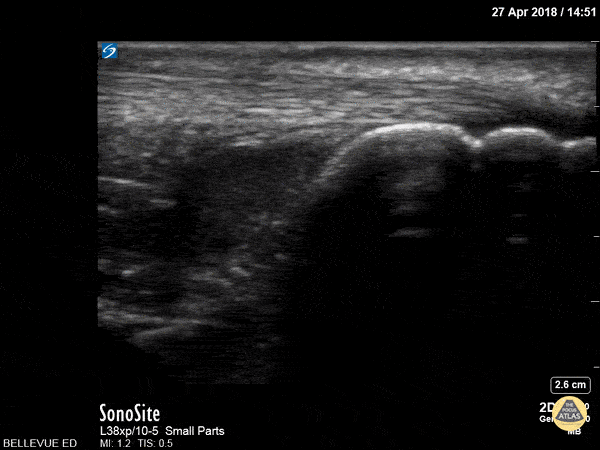

In this clip we see the linear, fibrillar, echogenic achilles tendon in long axis along the top of the screen. The clip begins distally at the tendon’s insertion onto the calcaneus (the curved hyperechoic structure on the right of the screen). As the probe is moved proximally, the gastrocnemius and soleus muscles become visible in long axis deep to the tendon. Hannah Kopinksi and Dr. Lindsay Davis - NYU Emergency Medicine